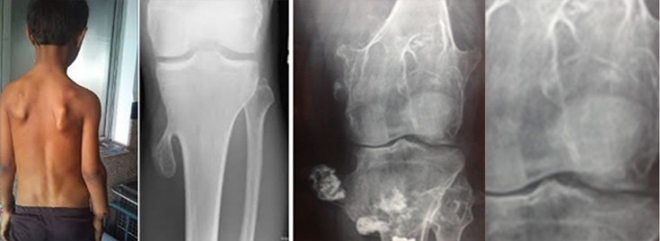

Η πάθηση έχει την ονομασία «πολλαπλές εξοστώσεις» γιατί συνήθως προσβάλλουν τα μακρά οστά και των άνω και των κάτω άκρων.

Οι εξοστώσεις των μακρών οστών ανευρίσκονται είτε τυχαία σε ακτινογραφία ρουτίνας ή είναι τόσο έκδηλα ψηλαφητές, ώστε ο ασθενής αναζητά εξήγηση για τον ψηλαφητό «όγκο» που νοιώθει στο γόνατό του.

Οι εξοστώσεις των μακρών οστών είναι συνήθως καλοήθεις διογκώσεις στο άκρο των μακρών οστών (βραχιονίου-κνήμης-πλευρών) οφειλόμενες στην ετερότοπη εγκατάσταση οστικών κυττάρων στην περίοδο της ανάπτυξης, συγχρόνως με την ανάπτυξη του γενικού σκελετικού χόνδρου. Γι’ αυτό και γίνονται συνήθως αντιληπτές στην εφηβεία.

Στην ψηλάφηση στο ένα ή και στα δύο πόδια, ψηλαφείται συνήθως στην έσω πλευρά του γόνατος μία σκληρή διόγκωση, που υπεγείρει το δέρμα. Δεν είναι επώδυνη στην ψηλάφηση ή την πίεση.

Αναδεικνύεται ευκρινώς στην απλή ακτινογραφία.